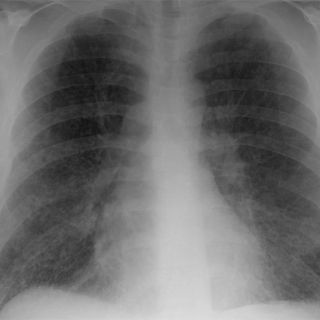

El primer estudio a realizar cuando existe sospecha de esta enfermedad es una radiografía, pero en algunos casos será necesario realizar una tomografía por emisión de positrones, que consiste en inyectarle a la persona un medio de contraste que ayudará a visualizar el crecimiento anormal de las células y su extensión.